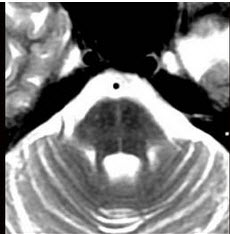

58、多项选择题

患者,男,55岁,渐起出现直立时头昏,直立性低血压2年,近半年出现眼球震颤、构音困难、步态不稳、共济失调、震颤及精神异常等症状,头颅MRI如图示,可采用的治疗方法为()